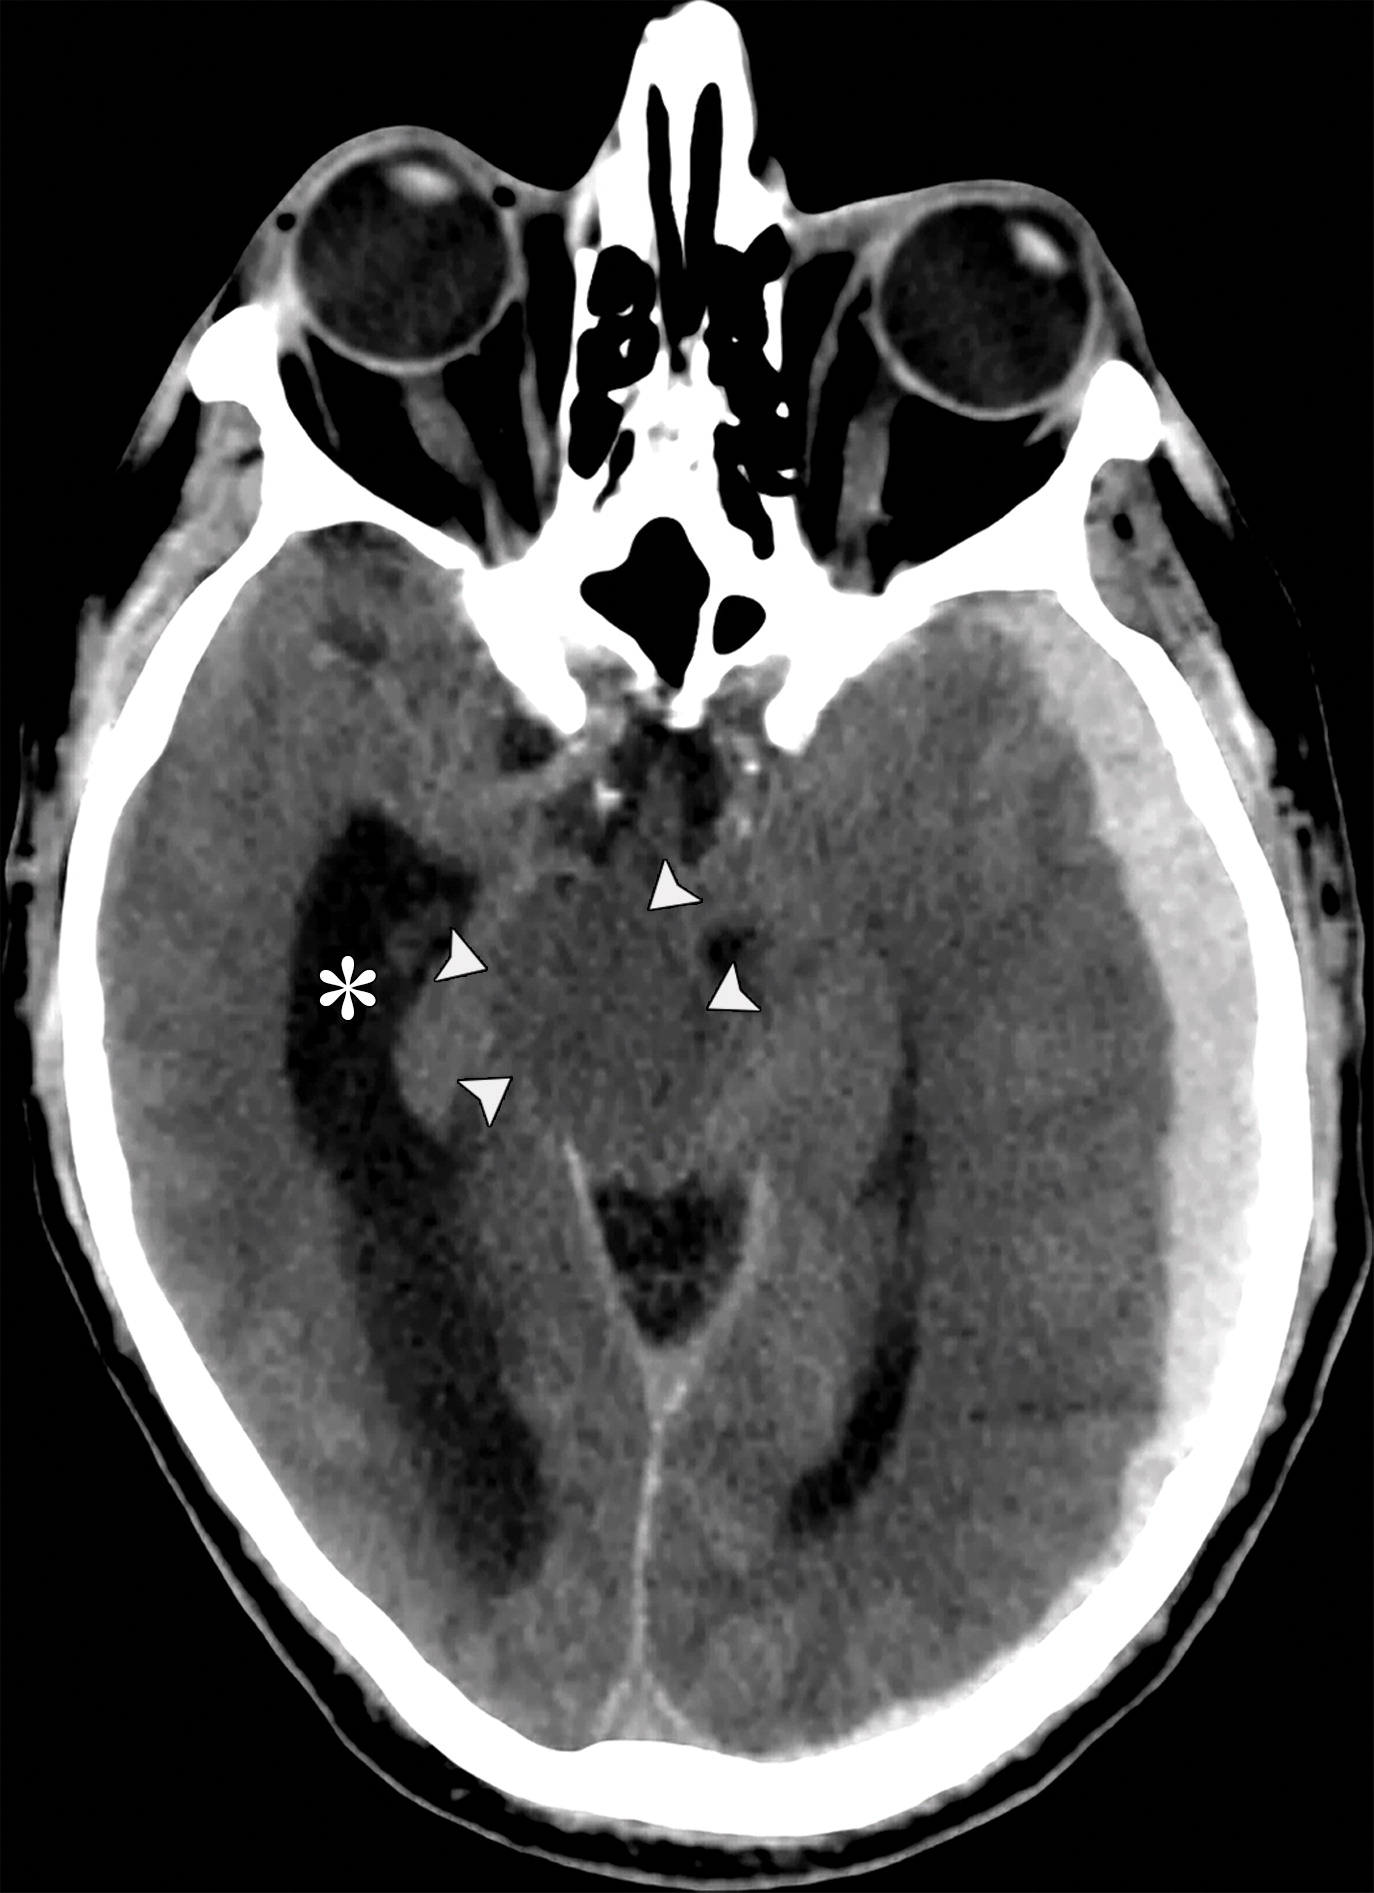

下降性小脑幕裂孔疝。左侧基底池增宽(白色长箭头),右侧基底池消失(白色虚线),右侧侧脑室的颞角扩张(*)。

cb72654f931b7e103fe4a14d193b2b5a.jpeg

下降性小脑幕裂孔疝。中脑受压,旋转,变长(白色短箭头)。中脑周围池完全闭塞。注意对侧侧脑室的增宽(*)。

cbe1ef133c421383c74d5ed9defc43e3.jpeg

26岁男性,终末期肾病血液透析后硬膜下血肿,右侧瞳孔扩张,对光反射消失。钩回向下跨越小脑幕切迹(白色弯曲箭头),同侧的中脑周围池增宽(白色双箭头),对侧中脑周围池受压。注意对侧侧脑室的颞角增宽(*)。